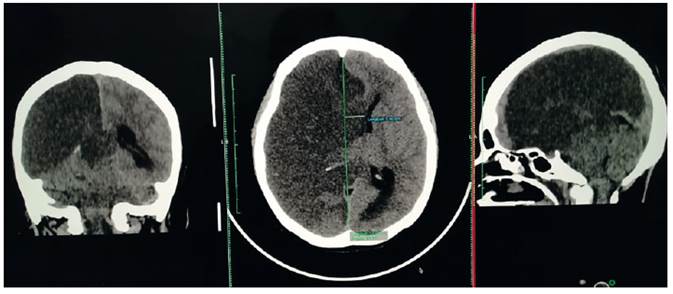

The objective of this communication is to present three cases of maternal death with SARSCoV-2 IgG / IgM (+), of the 36 occurred in Peru, treated at the Cajamarca Regional Teaching Hospital. They had severe preeclampsia and complications such as eclampsia and HELLP syndrome, with ischemic stroke, acute kidney injury, and hemorrhagic cerebrovascular disease. In addition, all had stillbirth.

Case 1: Ischemic stroke, eclampsia

A 32-year-old woman, 10-day puerperal with a 35-week stillbirth, and presenting high blood pressure and seizures, arrived from a distant health center in coma, with sepsis and pneumonia to COVID-19, As a background, she was G2 P0301 (one twin pregnancy) and had a positive contact with COVID-19 in her previous hospitalization 10 days before. She presented seizures, coma and left hemiplegia. The diagnosis was puerperal for 10 days, COVID-19 pneumonia, sepsis, right cerebral infarction, severe preeclampsia, eclampsia. The neurological diagnosis was score 20 according to the stroke score of the US Health Centers (NIH Stroke Scale- NIHSS).

The results of the laboratory tests were: reactive C protein: 96 mg/dL, complement 3: 289 mg/dL, complement 4: 90 mg/dL, sedimentation rate: 50 mm/h, SARS-CoV-2: IgG/IgM (+).

Brain multislice spiral tomography (MST) with coronal and sagittal reconstructions (Figure 1) showed extensive right cerebral infarction (in the middle cerebral artery (MCA) and the anterior cerebral artery (ACA) territory, with a large mass effect, conditioning deviation of the midline by 14 mm to the left and partial collapse of the supratentorial ventricles. Increase density of the MCA was evidenced, probably related to thrombus (Alberta Stroke Program Early CT Score (ASPECTS):0). Chest MST with coronal and sagittal reconstructions showed typical signs of Covid-19 ("ground glass", vascular thickening, cobblestone pattern, parenchymal bands and bilateral consolidations predominantly left). CORADS: 513.

Figure 1 Case 1. Brain tomography without contrast (with coronal and sagittal reconstruction): extensive rigth cerebral infarction (in the territory of the middle cerebral artery (MCA) and anterior cerebral artery (ACA)), with a large mass effect, conditioning a deviation of the midline by 14 mm to the left and partial collapse of the supratentorial ventricles. Increased MCA density is evidenced, probably related to thrombus (Alberta Stroke Program Early CT Score (ASPECTS ):0).

Treatment (see Table) included mechanical ventilation. During evolution, she presented seizures, auricular flutter, septic shock, kidney injury and died.

Figure 2 Case 1. Non-contrast chest tomography (with coronal and sagittal reconstruction) shows typical signs of Covid-19 - ‘ground glass’, vascular thickening, cobblestone pattern, parenchymal bands and bilateral consolidations, predominantly left. CO-RADS: 513.

Among the 36 maternal deaths in Peru due to COVID-19, we present three maternal deaths that occurred in Cajamarca, all with IgG/IgM (+) to SARS-CoV-2 and severe preeclampsia, two with eclampsia and two with HELLP syndrome. The first maternal death presented ischemic stroke (cerebral infarction). The second died of diabetes, kidney injury and pulmonary edema. The third, with eclampsia, HELLP syndrome and possible stroke. All three had a stillbirth of around 35 weeks.

Neurological symptoms due to COVID-19 range from anosmia to ischemic stroke or intracerebral hemorrhage. It is reported that due to hypercoagulability up to 5.7% of patients have cerebrovascular accident and 2.8% ischemic stroke15. Of hospitalized patients with COVID-19 and neurological compromise, 77% have an ischemic component. Because the complication occurs in the great vessels, 84.2% improve with Solumbra technique mechanical thrombectomy, obtaining substantial improvement in permeabilization, with score TICI> 2B/3 (16) . In our cases, coagulopathy with ischemic stroke was found in the territory of the right anterior and middle cerebral arteries in 33.3% of cases, associated with eclampsia and pneumonia due to COVID-19 (CORADS-5). In these cases, teamwork with neurology, neurosurgery, cardiology and radiology specialists is necessary, as well as the use of NIHSS clinical and ASPECT carotid arteries Doppler, cardiac Doppler radiological scales, and adequate thrombolysis, measurable with mTICI (modified treatment in cerebral infarction score), and early decompressive craniotomy.

In conclusion, there is still a lack of experience in the management of pregnant women in this pandemic. We consider that, first of all, pregnant women should be considered vulnerable and continue to control them without limitations.

Second, the possibility that preeclampsia be considered a comorbidity associated with mortality from COVID-19. Third, stillbirth may be common and should be considered and prevented. Fourth, severe preeclampsia in the presence of symptomatic COVID-19 has high mortality, due to the severity of both. Fifth, brain tomography is essential in early diagnosis and would help to quickly initiate the management of postpartum women with ischemic or hemorrhagic brain involvement.